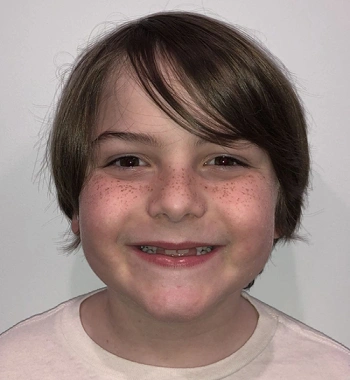

Actual Patient: Leanna

Before

Severe “Overbite”, BUCK TEETH, Narrow Jaws, Severe Deep Bite, Mouth breathing

Front View

Top View

Right & Left Sides

Treatment Time: 7.5 months